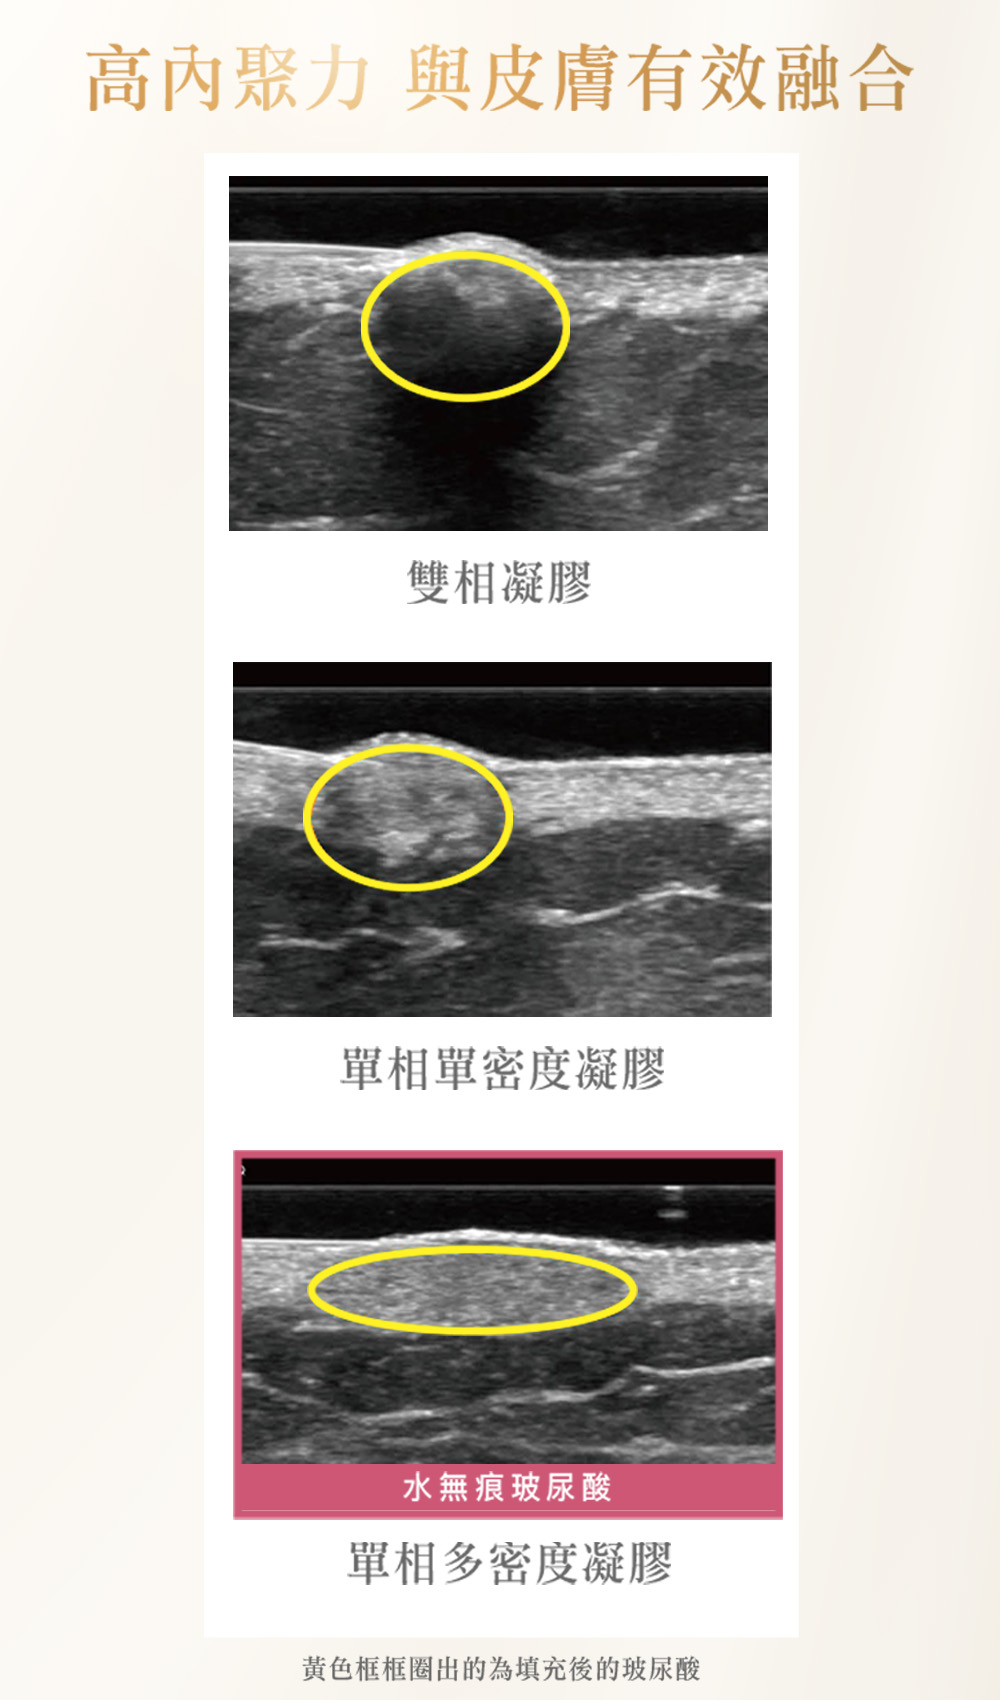

• 來自德國Merz藥廠的Belotero®保柔緹,又稱「水無痕玻尿酸」,具歐盟CE與美國FDA安全認證,並於多國臨床使用。以自然、平順為訴求,適合在意近看質感與細節的人。

• 採用獨家CPM (cohesive poly-densified matrix)單相多密度專利技術,呈現平滑且高內聚的凝膠結構,與真皮均勻貼合、邊界過渡更柔順,用於表層精修時更顯自然。

高融合貼真皮層

單相多密度凝膠具高內聚,能均勻鋪開,表面平順不顆粒;微笑說話也不易變形,線條自然柔和,適合追求近距離也好看的質感。

多密度順暢過渡

同支凝膠同時提供滑順與支撐,在小區域完成由平面到立體的銜接;特別適合法令與眼下等轉折處,邊界不生硬。